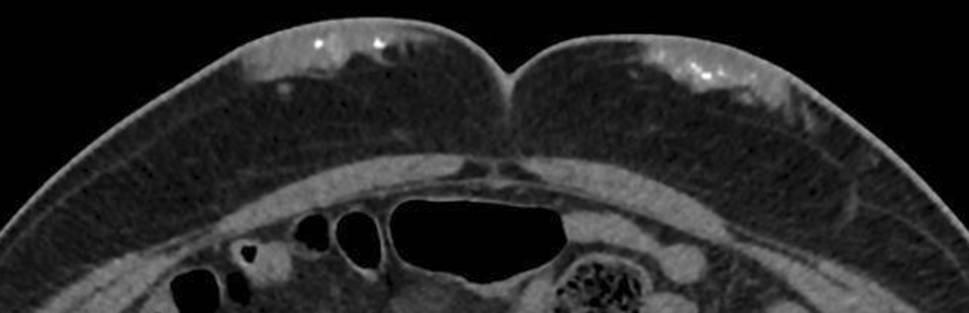

A 70-year-old patient presented to the traumatology department after he fell down the stairs. As an incidental finding the computed tomography (CT) scan showed bilateral, periumbilical subcutaneous alterations. These appeared to be soft tissue transformations with calcified sections, measuring approximately 4 cm (Fig. 1).

Fig. 1

CT scan, zoomed abdominal wall